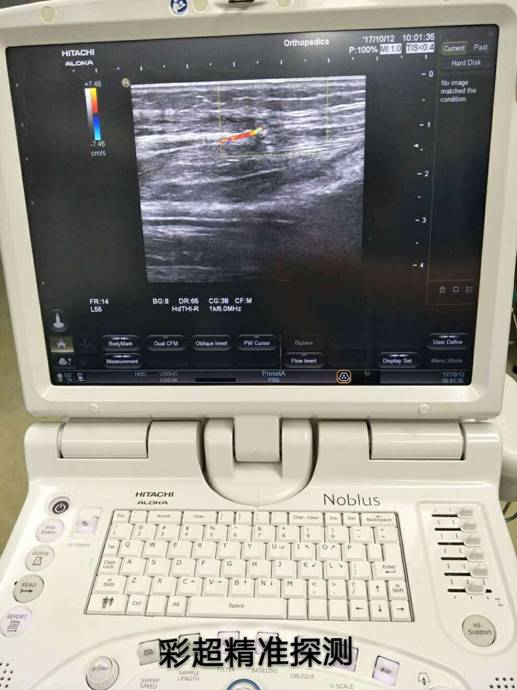

通訊員萬忠波 平國報道 粉碎性骨折+皮膚軟組織缺損+骨(肌腱)外露等損傷有了新療法,衡陽市中心醫(yī)院采用彩超精準定位、多學科協(xié)作施術,實現(xiàn)“大手術小創(chuàng)傷”。

近一個月來,衡陽市中心醫(yī)院收治了多位外傷導致小腿多處粉碎性骨折,小腿部分皮膚軟組織缺損、骨(肌腱)外露的患者,醫(yī)院燒傷整形科、骨科、超聲科多科協(xié)作,通過施行彩超定位下,小腿穿支皮瓣轉移修復創(chuàng)面手術,均取得良好的手術效果,極大地減輕了患者的疼痛和創(chuàng)傷。

骨科根據(jù)患者骨折情況分別施行骨折復位+內(外)固定術,然后由燒傷整形科根據(jù)患者皮膚軟組織缺損情況,制定小腿穿支皮瓣轉移修復創(chuàng)面方案。為保證手術成功率,燒傷整形科會同超聲科由黃道遠主任于術前利用彩超精準的探測小腿術區(qū)的各個動脈穿刺,并逐一標記,再由燒傷整形科手術團隊根據(jù)動脈穿支的分布情況設計皮瓣,施行小腿穿支皮瓣轉移修復術。

由于采用了彩超定位技術,使得皮瓣設計方案更合理,手術操作更精準,手術耗時更少,更因為保護好了血管,術后皮瓣腫脹,存活均較以往有明顯改善,手術效果得到極大保障,患者滿意度大大提高。